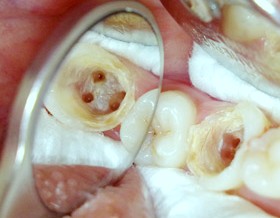

Cara Mengobati Sakit Gigi Berlubang Besar

Cara mengobati sakit gigi berlubang besar. Alasan itulah saya menyempatkan. Salah satu cara mengobati sakit gigi berlubang yang ampuh adalah dengan garam. Umumnya penyebab sakit gigi berlubang adalah plak yaitu zat lengket di mulut yang sebagian besar tercipta akibat adanya tumpukan kuman atau bakteri yang mengubah makanan menjadi asam.

Cara mengobati sakit gigi berlubang ini khusus buat sobat yang mengalami lubang pada gigi anda namun jika sebelum sobat mendapati lubang pada gigi sebaiknya cegah sejak mula dengan membersihkan gigi secara teratur namun bila anda sudah mendapati lubang pada gigi anda dan ini mendatangkan rasa sakit mungkin beberapa tips pengobatan alami gigi berlubang ini bisa membantu anda menuntaslan. Kemudian asam pada plak bisa merusak enamel pelindung gigi hingga membuat gigi berlubang. Sakit gigi memang sangat merepotkan dan tentunya mengganggu aktipitas penderitanya.